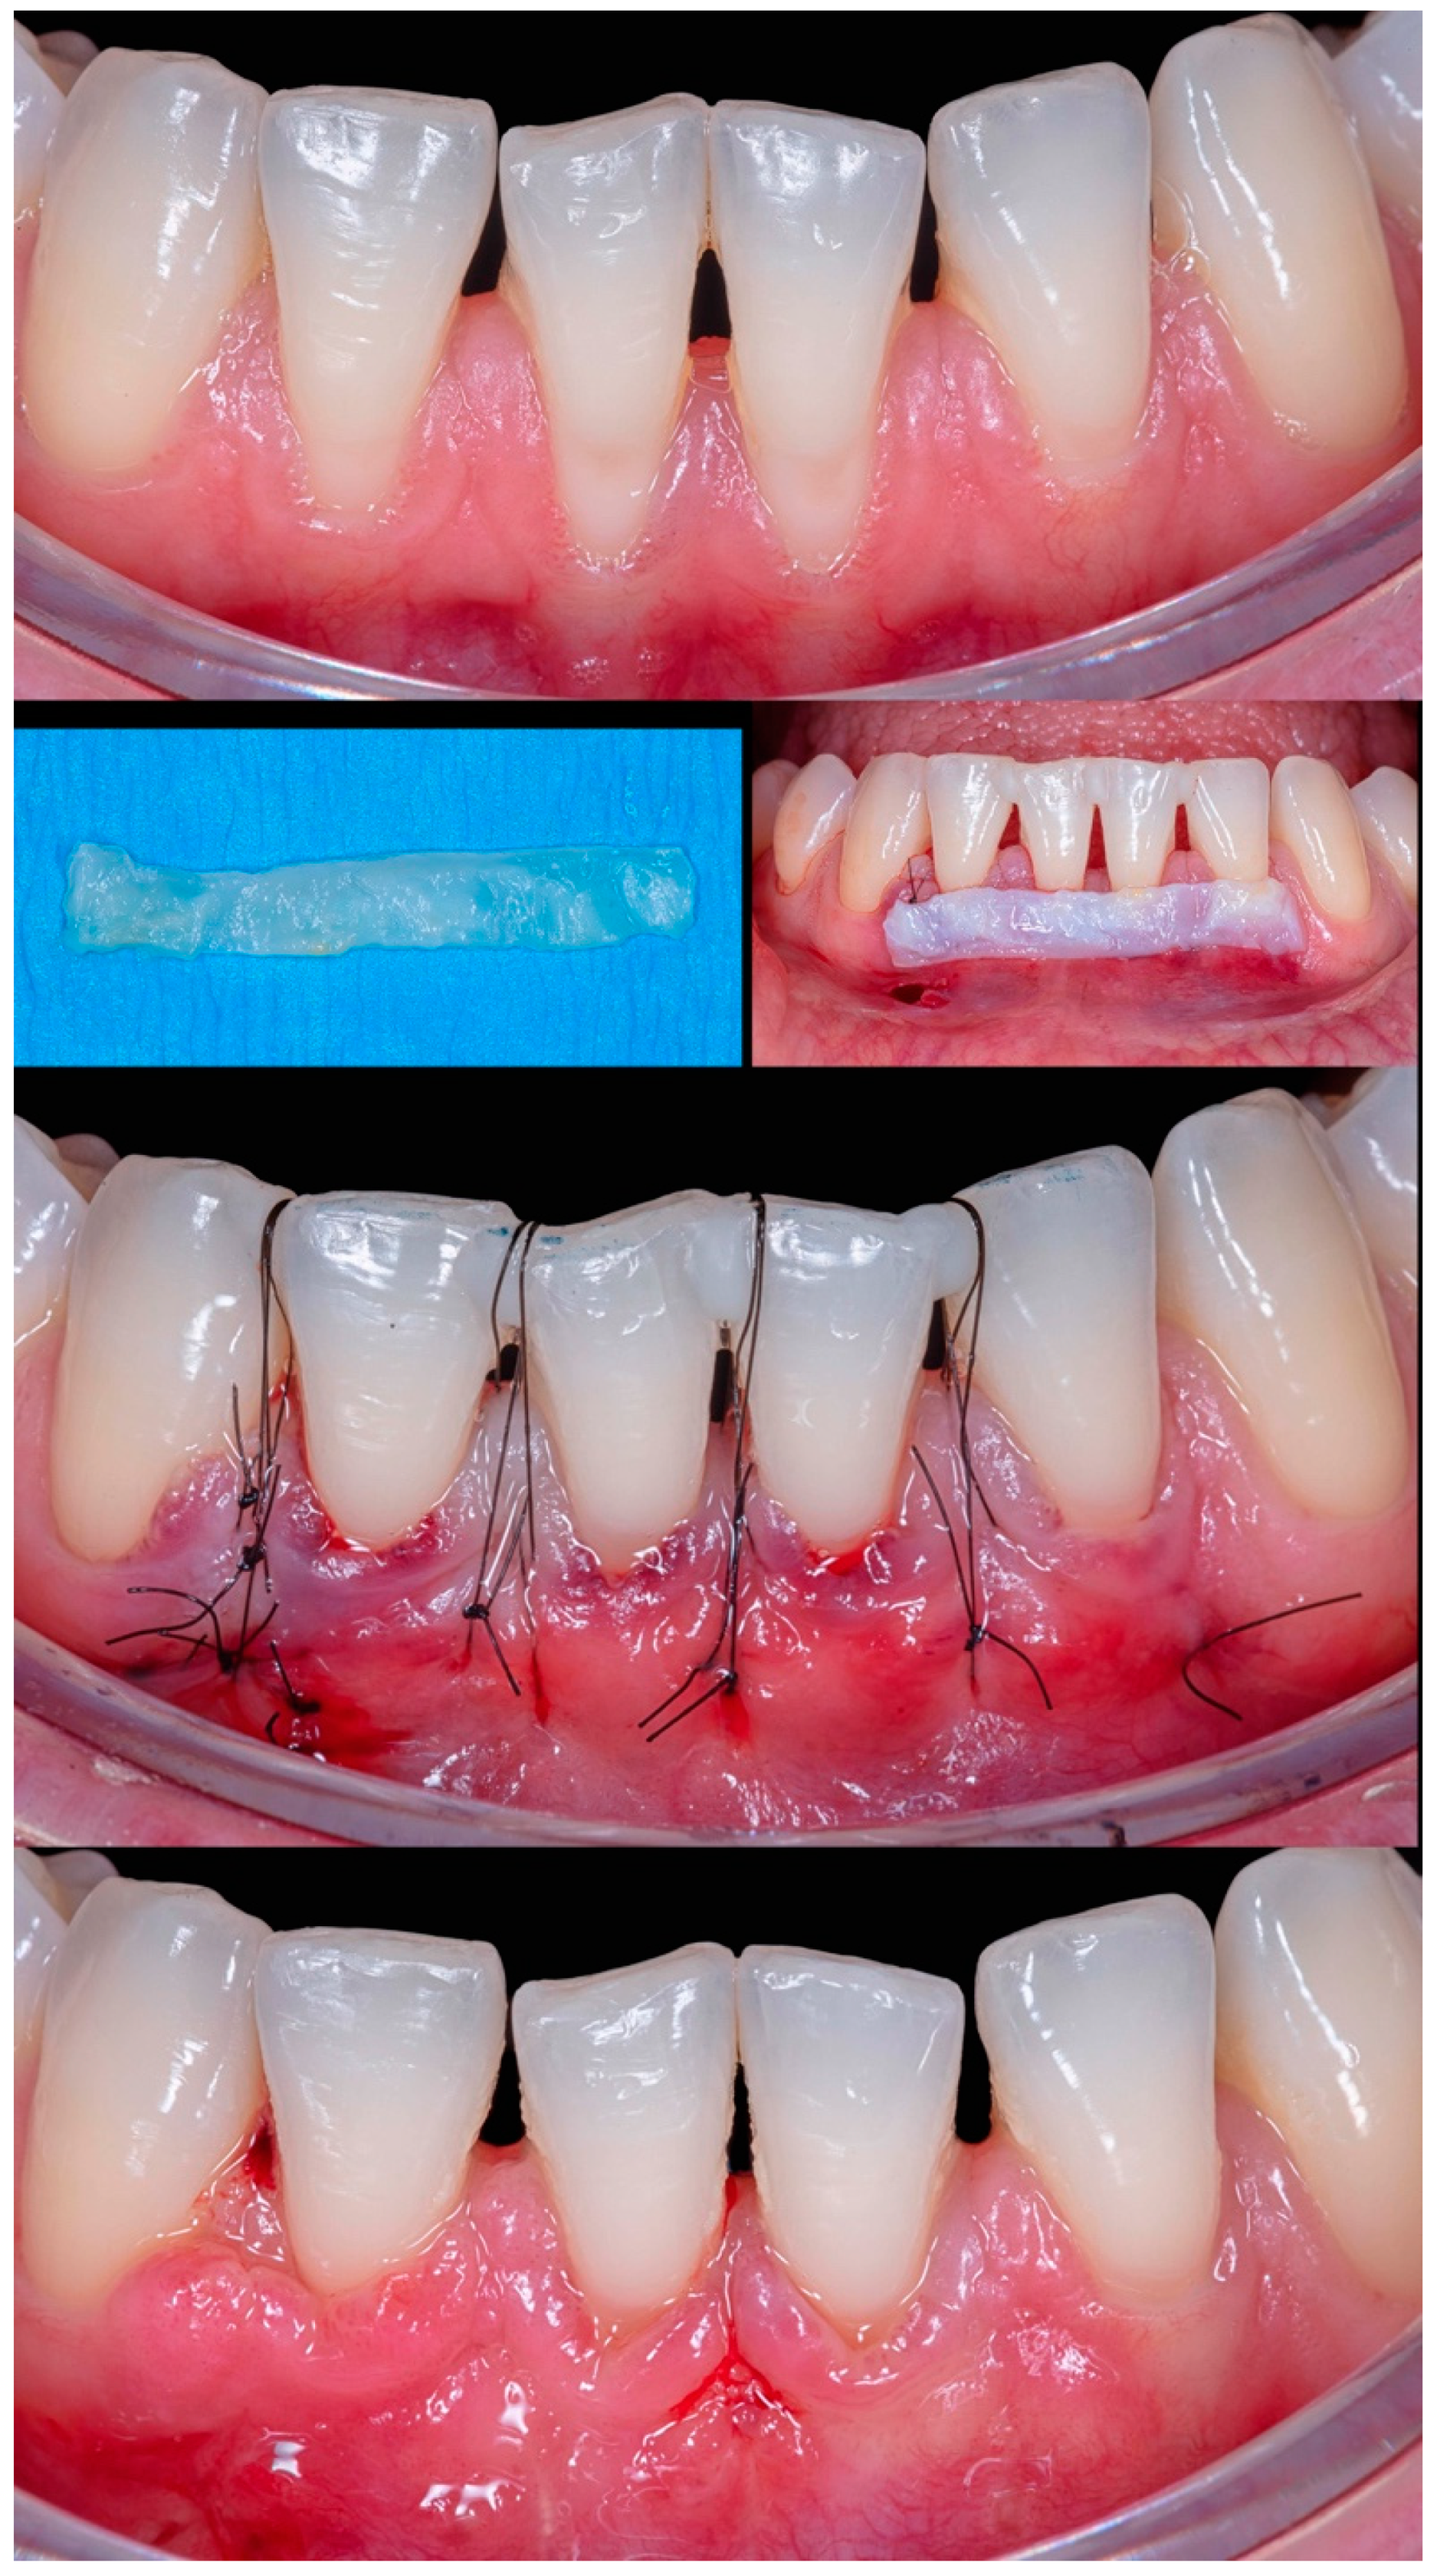

Figure 8) differed from the rest because it involved an esthetic area in an anterior maxillary region. Even with a gingival RT1 in teeth #12-#22, respectively, with 1mm, 1.5mm, 2mm, and 1.5mm, teeth #11 and #21 presented a wide GR (3mm and 4mm, respectively). The case was conducted without adverse events using two linear vertical incisions on the distal to the central incisors. A buccal suture in the facial region of the teeth was made using composite. An adequate healing process was found after 7 days and 1 year, which was permitted by the tissue stability achieved in soft tissue management. The success rate was 100% for RC.

Figure 8.

Case 7 shows initial pictures of the GR defects (#12-#22); a picture showing the final aspect immediately after surgery; and the healing period after 14 days and 1 year.